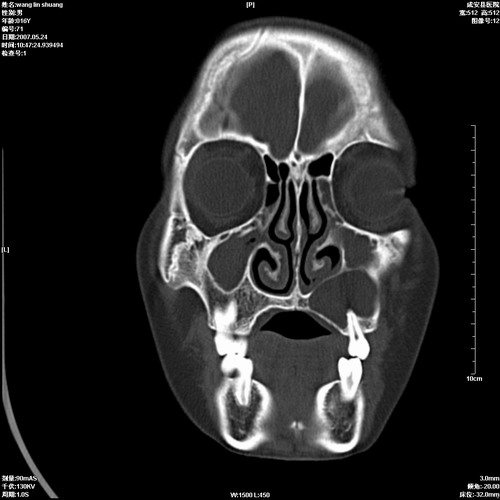

病人,男 16岁,鼻旁右肿胀,其余无不适感,ct图片

1、典型右侧根尖囊肿。

2、双侧上颌窦、筛窦、蝶窦炎

1\\左侧上颌骨含牙囊肿

2\\两上颌窦炎

右侧上颌骨含牙囊肿.双侧上颌窦炎症.

右侧上颌骨含牙囊肿.双侧上颌窦、蝶窦右侧炎症.

1、左侧上颌骨含牙囊肿。